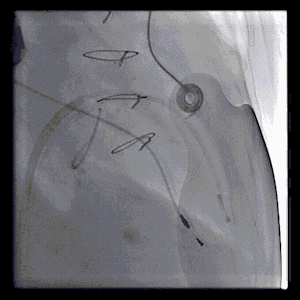

RAO:23° CRA:25°

Positioning heigh: 90/10 preferred